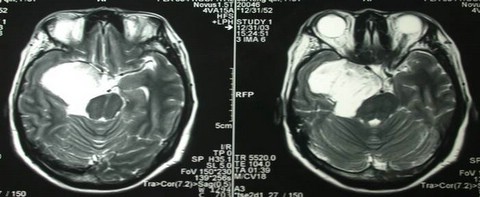

右CPA胆脂瘤

女性,49岁,右侧外展、动眼神经完全麻痹入院。右中颅窝巨大占位性病变。